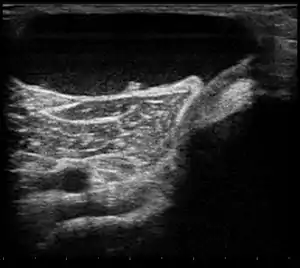

| Ultrasound image of Baker's cyst | |

Risk factors include other knee problems such as osteoarthritis, meniscal tears, or rheumatoid arthritis.[1][3][4] The underlying mechanism involves the flow of synovial fluid from the knee joint to the gastrocnemio-semimembranosus bursa, resulting in its expansion.[1] The diagnosis may be confirmed with ultrasound or magnetic resonance imaging (MRI).[3]

Diagnosis is by examination. A Baker's cyst is easier to see from behind with the patient standing with knees fully extended. It is most easily palpated (felt) with the knee partially flexed. Diagnosis is confirmed by ultrasonography, although if needed and there is no suspicion of a popliteal artery aneurysm then aspiration of synovial fluid from the cyst may be undertaken with care. An MRI image can reveal presence of a Baker's cyst.